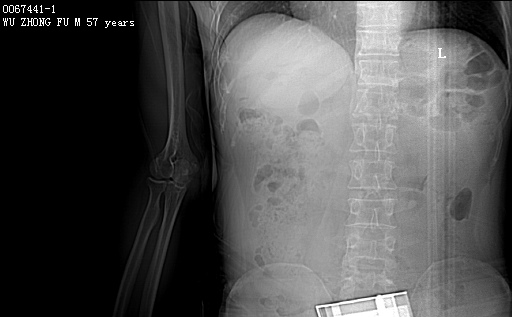

CT50131:M,57y。发现右肘包块10年,左肘包块3月。

【结果公布】 【左肘关节CT】 男,57岁。发现右肘包块10年,左肘包块3月。 PE:无。 临床诊断:双肘部肿物(性质待查)。 右肘关节CT轴位平扫(层厚5mm,层距5mm)图像如下: ...

双侧肘关节痛风性关节炎(痛风石形成);建议查血尿酸。

痛风性关节炎

CT50132、CT50131: 双侧肘关节痛风性关节炎(痛风石形成)。